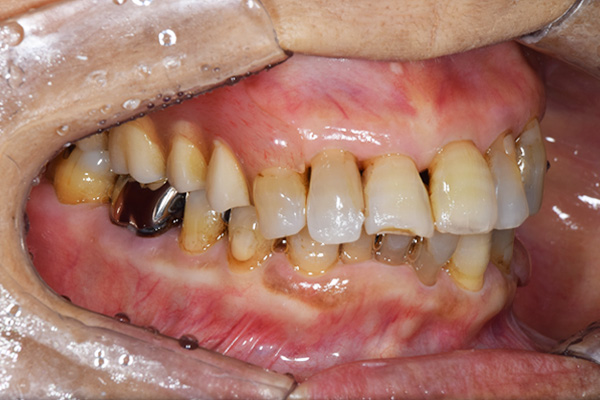

前歯が折れて当院にいらっしゃいました。 過去に下の入れ歯を作ったが、合わなくなってずっと入れ歯をいれていらっしゃらない患者様でした。 これは奥歯で噛むことができないため、前歯で噛むことを繰り返したために、負担に耐えられなくなった前歯が折れてかぶせ物ごと 外れてしまったのだと考えられます。 痛くない、違和感の少ない、下の入れ歯を作ることがこの方のゴールであると考えられました。

シリコンで精密な型取りを行いました。

噛み合わせチェックです。 奥歯でしっかりものが噛める様に高さを決めていきました。

金属を使用して、薄く違和感が少ない入れ歯が完成しました。 また、見た目にも気を使い、バネが見えにくい様な構造にしました。

入れ歯をお口の中にいれた状態です。前歯もMTMといって、歯を少し引っ張り出す処置を行なったことで、しっかり残せて、またかぶせ物をしました。

年齢 70歳・女性

主訴 前歯が取れた

治療期間 8ヶ月

治療費 .MTM:110,000円

.ファイバーコア:16,500円

.E-maxクラウン:110,000円

.義歯:660,000円

治療方針 長年使ってきた義歯の人工歯が磨耗し、臼歯部での咬合がすくなくなり、前歯部での接触が強くなったことで生じた前歯の破折なので、義歯も作り変える必要がある。

治療内容 前歯部MTMと同時に審美面の回復。

MTM中に義歯の作成も同時に行う。

最終的に義歯と前歯のクラウンを同時にいれる。

義歯は下顎で、しっかり噛めること、違和感の少ないものという希望があったため、なるべく入れ歯を薄く作成するために金属をしようした義歯とした。

また、見た目もあまり義歯が目立たない様に、バネの部分を見えにくいように作成した。

特記事項 歯にもともと入っていた金属の種類によっては、歯自体の変色を治療で変えられないこともある。 義歯は作ってから痛みがでることがありますが、それは調整を行うことで痛くなくすることができます。